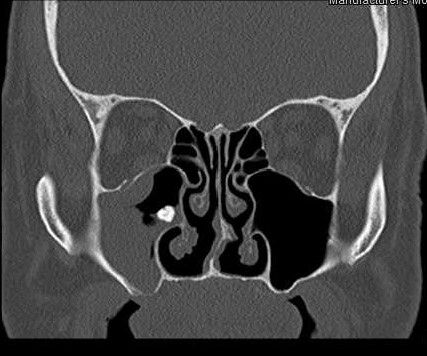

La comunicación oroantral (COA) o comunicación bucosinusal (CBS), se define por la ruptura de las barreras anatómicas presentes entre el seno maxilar y la cavidad oral, habitualmente a nivel del alveolo de un diente antral extraído (Figura 1). Las extracciones dentales son la principal causa de COA, con una incidencia del 0,3 – 4,7% de las extracciones y representan el 95% de los casos de COA 9. La fístula oroantral (FOA) corresponde a una COA que permaneció permeable y se epitelizó porque no se cerró espontáneamente, o no se ha tratado adecuadamente. Según varias revisiones sistemáticas y metaanálisis, se afirma que la COA representa la causa más común de SO 7.

Distinguir radiográficamente un seno sano de uno enfermo no es tan problemático teniendo en cuenta su forma, que es inconsistente, con muchos lobulaciones, por lo tanto, en caso de sinusitis, se puede observar opacificación, engrosamiento de la mucosa y/o acumulación de líquido 17(Figura 3).